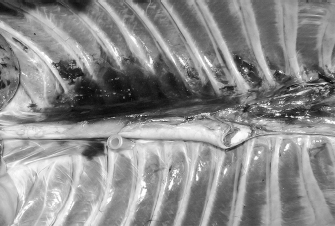

Fig. 7. NMB and ioversol longitudinal ipsilateral thoracic paravertebral spread in a dog cadaver. Ventral view.

Although with some minor intra- and inter-specific differences, a positive air-LOR test was associated with longitudinal spread along the extrapleural compartment of the TPVS in 100% of the animals. In dog cadavers, the median injected volume (ml kg−1) of the mixture was 0.6 ml (0.22–1.25). The lateral thoracic radiographs showed multi-segmental spread in 100% of the subjects, with a median of 4.5 (2–10) vertebrae and a distribution of 2.5 (0–7) vertebra cranial and 1.0 (0–3) vertebra caudal to the injection level. A longitudinal spread pattern was noted on all radiographs, mixed with a cloudy pattern in 11/14 (78%) images and with an intercostal pattern at the level of the ninth intercostal space in 1/14 (7%) image (Fig. 6). Necropsy revealed multi-segmental ipsilateral longitudinal spread in 100% of the subjects (Fig. 7). The median stained intercostal spaces were 6.5 (4–11), with 5 or more spaces stained in 78%, whereas contralateral longitudinal spread was detected in 9/14 (64.3%) spaces, with a median of 2.5 (0–6) (Fig. 8). The median cranial versus caudal spread ipsilateral and contralateral to the injection site was 3 (1–7) versus 2 (0–3) and 0 (0–4) versus 1 (0–2) space, respectively. Distributions of NMB and ioversol after each mixture injection are shown in Figure 9. The only statistically significant correlation was between the radiographical and the necroscopic assessment of the longitudinal spread in the dog cadavers ( p=0.0028).